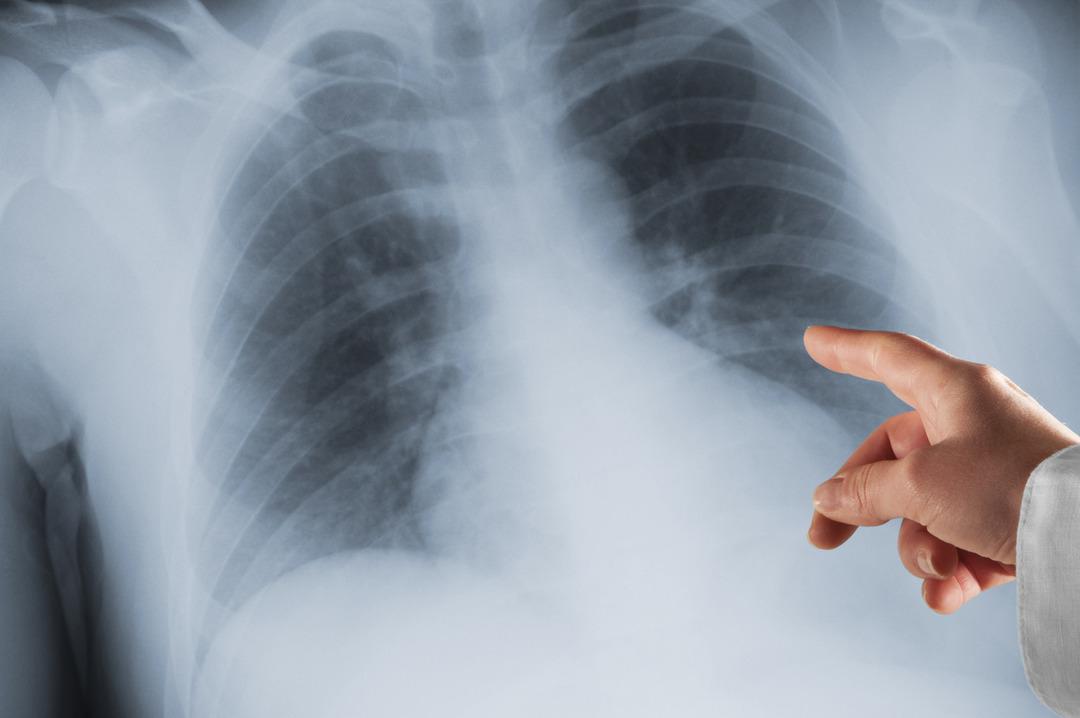

Akciğer kanseri dünyada en sık görülen kanser türlerinden biri olmasına rağmen, hastalığa ilişkin farkındalığı artırmak amacıyla Kasım ayı “Akciğer Kanseri Farkındalık Ayı”, 17 Kasım ise “Akciğer Kanseri Farkındalık Günü” olarak kabul ediliyor. Tütün ve tütün ürünlerinin tüketiminin yanı sıra hava kirliliği de hastalığın nedenleri arasında yer alıyor.

Türk Tıbbi Onkoloji Derneği Üyesi ve Tıbbi Onkoloji Uzmanı Doç. Şahin Laçin, dünyada her yıl 2,5 milyon, Türkiye’de ise 45 bin civarında yeni vaka görüldüğünü, bu verilerin akciğer kanserini özellikle erkeklerde, kadınlarda ise ilk sıraya koyduğunu söyledi.

Akciğer dokusunda ağrılı liflerin bulunmaması nedeniyle kanserin ileri evrede tespit edilebildiğini vurgulayan Kömürcüoğlu, hastalığın olası belirtilerini mevcut öksürüğün şeklinin değişmesi, artması veya devam etmesi, öksürükle birlikte balgamın da çıkması, özellikle balgamda kan görülmesi, nefes darlığı, halsizlik, iştahsızlık ve istemsiz kilo kaybı, boyun veya göğüs duvarında şişlik veya asimetri, sebepsiz ağrı olarak sıraladı.